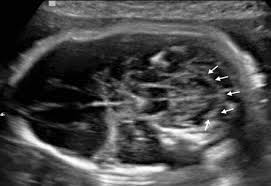

This fetus of a G1P0 mother presented to your office for this imaging on routine 3rd trimester scan

What is an intraventricular hemorrhage?